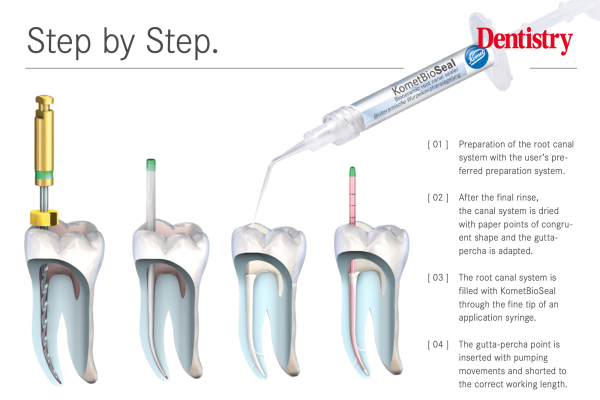

KometBioSeal – the new bioceramic root filling sealer

KometBioSeal is a new root filling sealer from Komet Dental that creates the perfect bond between filling material and root…